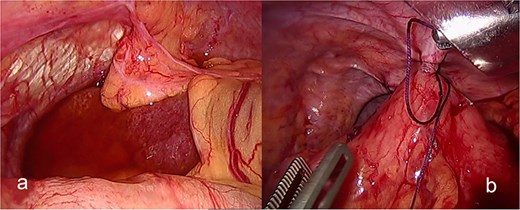

The patient was admitted under the care of the general surgery department, and he was taken to the operating room for a laparoscopic exploration, which showed mesenteroaxial gastric volvulus, wandering spleen, and a large hiatal hernia which was ~5 cm in size. No devitalized tissues were found. An attempt at intraoperative endoscopy failed to pass through the hiatus. A cruroplasty with a Toupet fundoplication and gastropexy were done as shown in (Figs 3 and 4). On the third postoperative day, the patient was doing well. He was tolerating oral intake and passing regular motions and was discharged home in good condition as he was traveling to his country.

(a) Intraoperative image revealing the position of the stomach without any devitalized tissue. (b) A large hiatal hernia after completion of dissection in preparation for cruroplasty with a Toupet fundoplication.